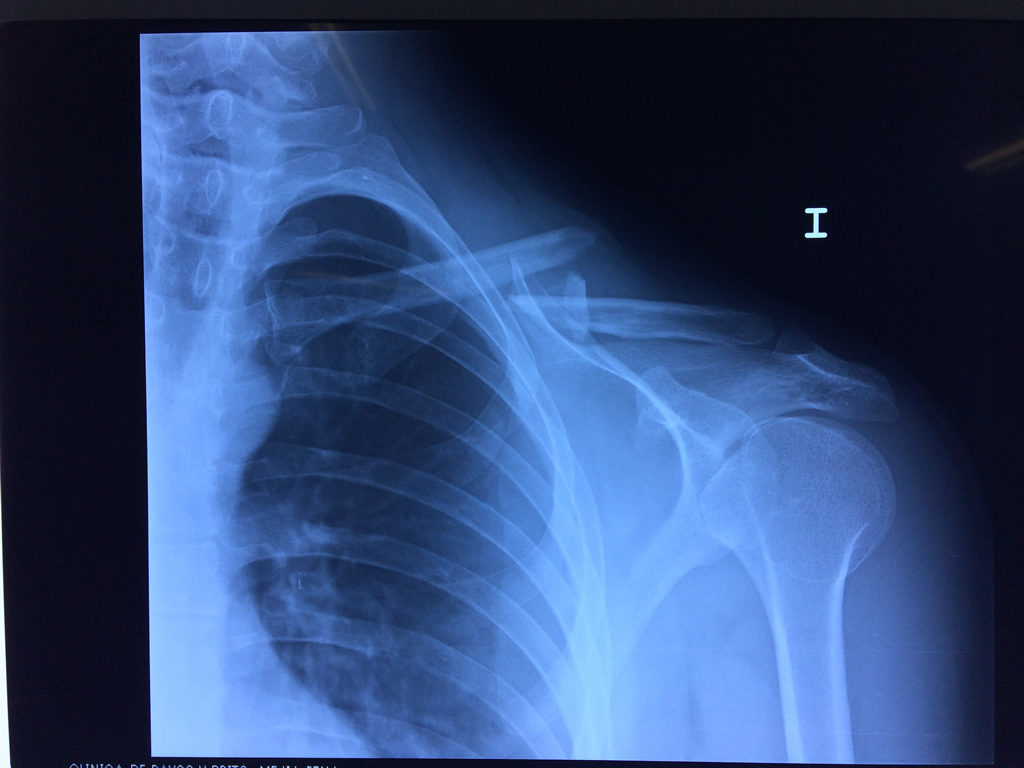

Cirugías de Hombros - Clavícula

La clavícula es un hueso largo, con forma de "S" itálica, situado en la parte anterosuperior del tórax. Junto con la escápula forman la cintura escapular. Se puede palpar por toda su longitud y se extiende del esternón al acromion de la escápula, siguiendo una dirección oblicua lateral y posterior.